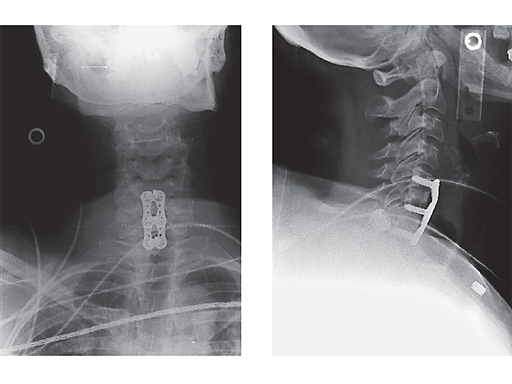

Postoperative x-rays of a case treated with Vectra in which this 60-year-old female underwent discectomy and interbody grafting for C56, 67 stenosis with radiculopathy.

Vectra is a flexible and easy-to-use plating system for the semi-constrained fixation of the anterior cervical spine. Vectra allows surgeons to combine fixed-angle and variable-angle screws as required, and therefore gives more freedom to build a safe construct that is appropriate to the individual situation. Variable-angle screws allow the platescrew-construct to move minimally so that it can compensate for postoperational subsidence. Meanwhile the construct maintains stability and keeps the screws contained in the plate. Fixed-angle screws, on the other hand, restrict motion.